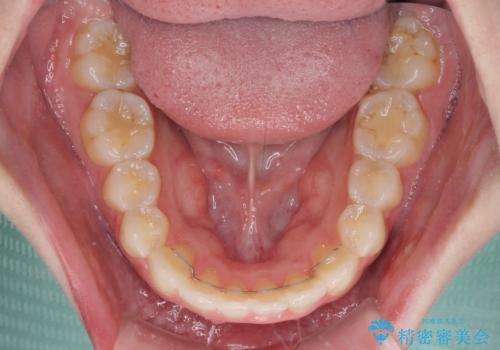

抜歯矯正の後戻り インビザラインによるオープンバイトの再矯正

- 以前矯正治療をされていましたが、後戻りが起きたことを気にして来院された患者様です。

上下前歯のオープンバイトを改善するため、インビザラインにて治療を行うこととしました。

外食が楽しみである患者様だったので、インビザラインによる治療期間は我慢の時期であったようです。

自己管理を徹底していただいたので、1年程度で治療を終えることができました。